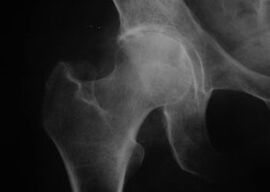

Coxathrosis, arthrosis of the hip joint

With this disease, the clinical clinical picture of arthrosis is observed.

The first symptom of coxarthrosis is discomfort in the hip joint after physical activity.

With progressive coxarthrosis, increased pain, stiffness and limited movement appear.

Patients with a severe form of coxarthrosis release the affected limb, avoid stepping on it, and while stationary, choose a position where the pain is felt the least.